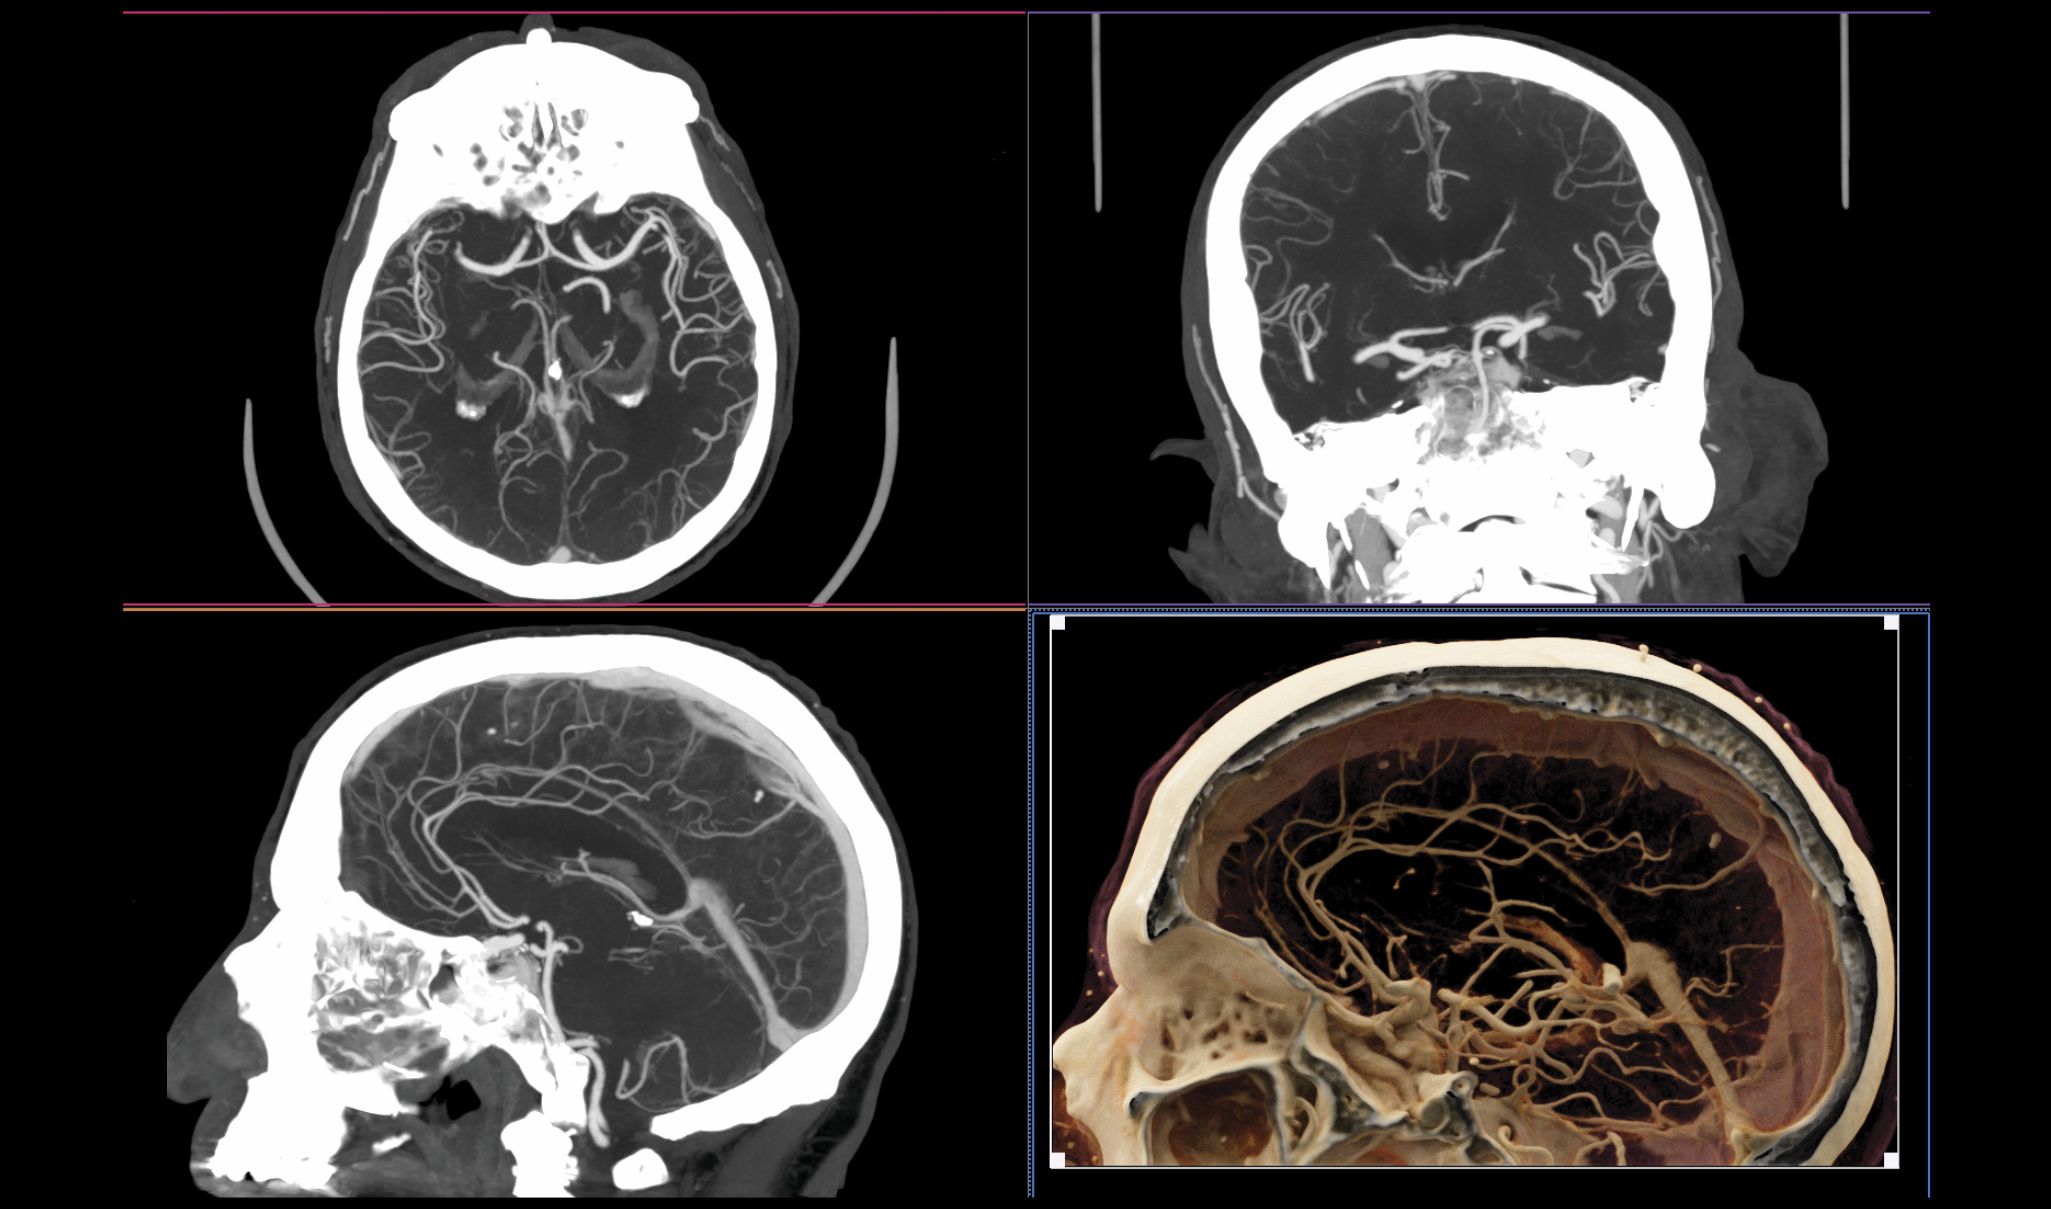

Figure 4.

Blood vessels in the brain. Once referred to as CAT (computed axial tomography) scanners because the data were acquired and reconstructed in the axial plane, modern CT systems have submillimeter detector pixels along the